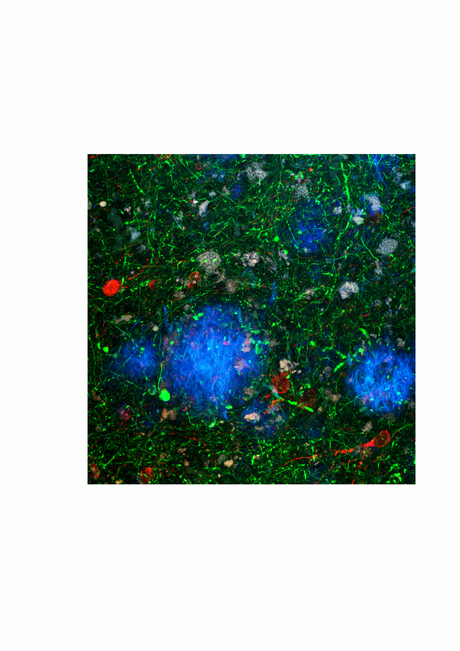

In a study published this year in the Journal of Neurochemistry, his team looked at synapse vulnerability in Alzheimer’s disease, both in human brain tissue at different pathological stages and in a commonly used transgenic model. It turned out that the transgenic mice developed the characteristic Alzheimer’s plaques in their brains but did not exhibit much neuronal degeneration, which is reminiscent of preclinical disease in humans before the dementia symptoms become really obvious.

Their analysis also revealed similar levels of synapse loss in brains from people with early-stage disease and those of the transgenic mice.

“So, rather than just saying something about established or end-stage disease, the whole story became so much more important for potential early interventions as a result of bringing in the human tissue comparison,” said Vickers. “Indeed, most of the transgenic models used in this field are not full models of Alzheimer’s disease but probably represent specific stages of the disease.”